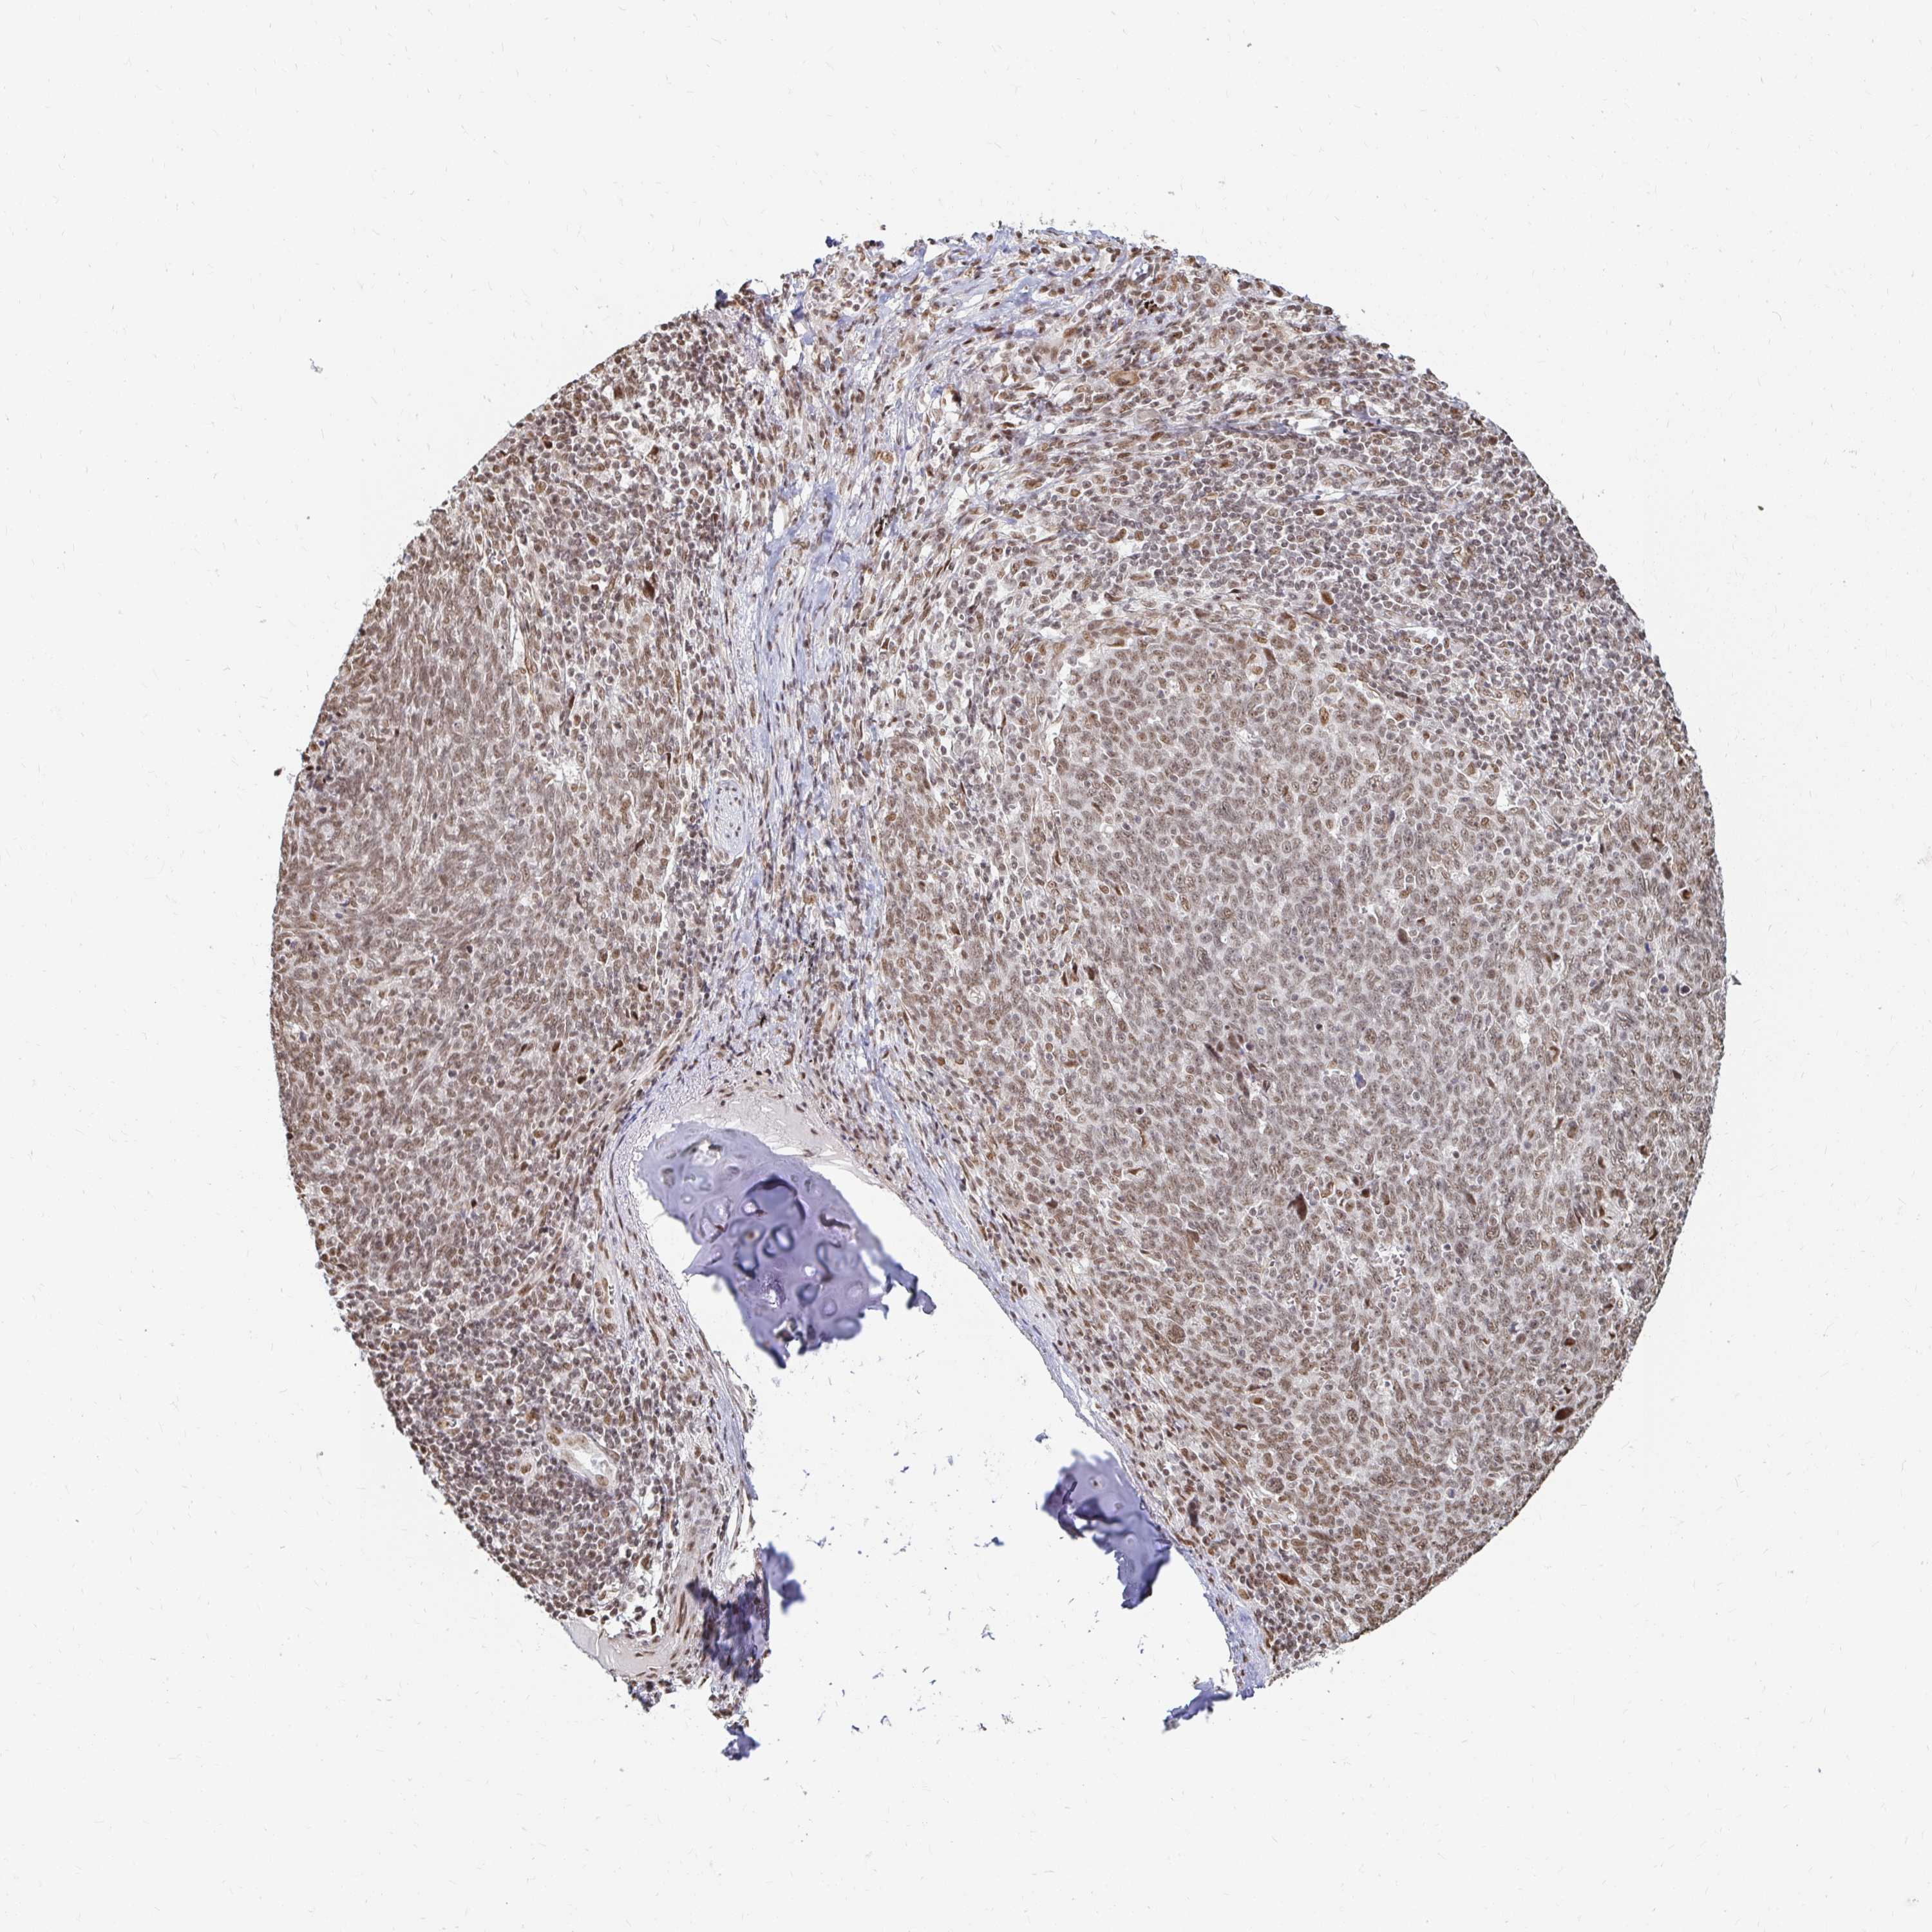

LUNG ADENOCARCINOMA (TCGA) - Interactive survival scatter ploti

The Survival Scatter plot shows the clinical status (i.e. dead or alive) for all individuals in the patient cohort, based on the same data that underlies the corresponding Kaplan-Meier plots. Patients that are alive at last time for follow-up are shown in blue and patients who have died during the study are shown in red.

The x-axis shows the expression levels (FPKM) of the investigated gene in the tumor tissue at the time of diagnosis. The y-axis shows the follow-up time after diagnosis (years). Both axes are complimented with kernel density curves demonstrating the data density over the axes. The top density plot shows the expression levels (FPKM) distribution among dead (red) and alive patients (blue). The right density plot shows the data density of the survived years of dead patients with high and low expression levels respectively, stratified using the cutoff indicated by the vertical dashed line through the Survival Scatter plot. This cutoff is automatically defined based on the FPKM cutoff that minimizes the p-score. The cutoff can be changed by dragging the vertical line or by entering a cutoff value in the square labeled "Current cut-off".

Under the Survival Scatter plot the p-score landscape (black curve; left axis) is shown together with dead median separation (red curve; right axis). Dead median separation is the difference in median mRNA expression between patients who have died with high and low expression, respectively. It is calculated as follows: median FPKM expression of dead patients with high expression - median FPKM expression of dead patients with low expression. This is intended to aid the user in visually exploring custom cutoffs and the associated p-scores and dead median separation.

Individual patient data is displayed and can be filtered by clicking on one or more of the category buttons on the top of the page. Categories describing expression level and patient information include: high, low, alive, dead, female, male and tumor stages. The scale of the x-axis can be toggled between linear and log-scale by clicking on the "x log" button. Mouse-over function shows TCGA ID, patient information and mRNA expression (FPKM) for each patient.

& Survival analysisi

Kaplan-Meier plots summarize results from analysis of correlation between mRNA expression level and patient survival. Patients were divided based on level of expression into one of the two groups "low" (under cut off) or "high" (over cut off). X-axis shows time for survival (years) and y-axis shows the probability of survival, where 1.0 corresponds to 100 percent.

HNRNPU is potential prognostic, high expression is unfavorable in Lung Adenocarcinoma (TCGA)

Best expression cut offi

Based on the FPKM value of each gene, patients were classified into two groups and association between prognosis (survival) and gene expression (FPKM) was examined. The best expression cut-off refers the FPKM value that yields maximal difference with regard to survival between the two groups at the lowest log-rank P-value. Best expression cut-off was selected based on survival analysis .

When clicking on this number, the vertical dashed line indicating cut-off, the interactive survival plot, and the Kaplan-Meier curve will be adjusted to show results based on the best expression cut-off.

: 166.44

P scorei

Log-rank P value for Kaplan-Meier plot showing results from analysis of correlation between mRNA expression level and patient survival.

N/A

TCGA RNA samplesi

RNA-seq data is reported as average FPKM (number Fragments Per Kilobase of exon per Million reads), generated by the The Cancer Genome Atlas (TCGA) .

Normal distribution across the dataset is visualized with box plots, shown as median and 25th and 75th percentiles. Points are displayed as outliers if they are above or below 1.5 times the interquartile range. FPKM values of the individual samples are presented next to the box plot.

Average pTPM 168.9

Number of samples 497